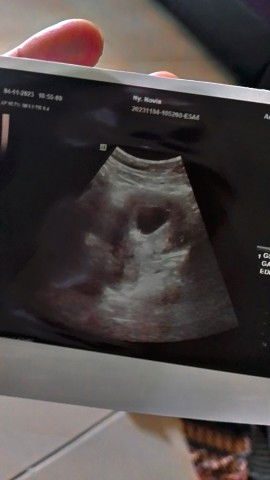

kebobolan saat anak usia 10 bulan

moms mau cerita, rasanya melahirkan masih terasa bgt eh uda mau rasain lahiran lagi, anak aku baru 10 bulan, baru juga merasakan istirahat, anak tidurnya uda gapernah bangun malem, eh malah mau terulang lagi masa masa itu, sedih bgt moms, harusnya kabar kehamilan itu membahagiakan, ini malah jd sedih buat aku dan keluarga, kasian anak aku masi bayi #bantusharing